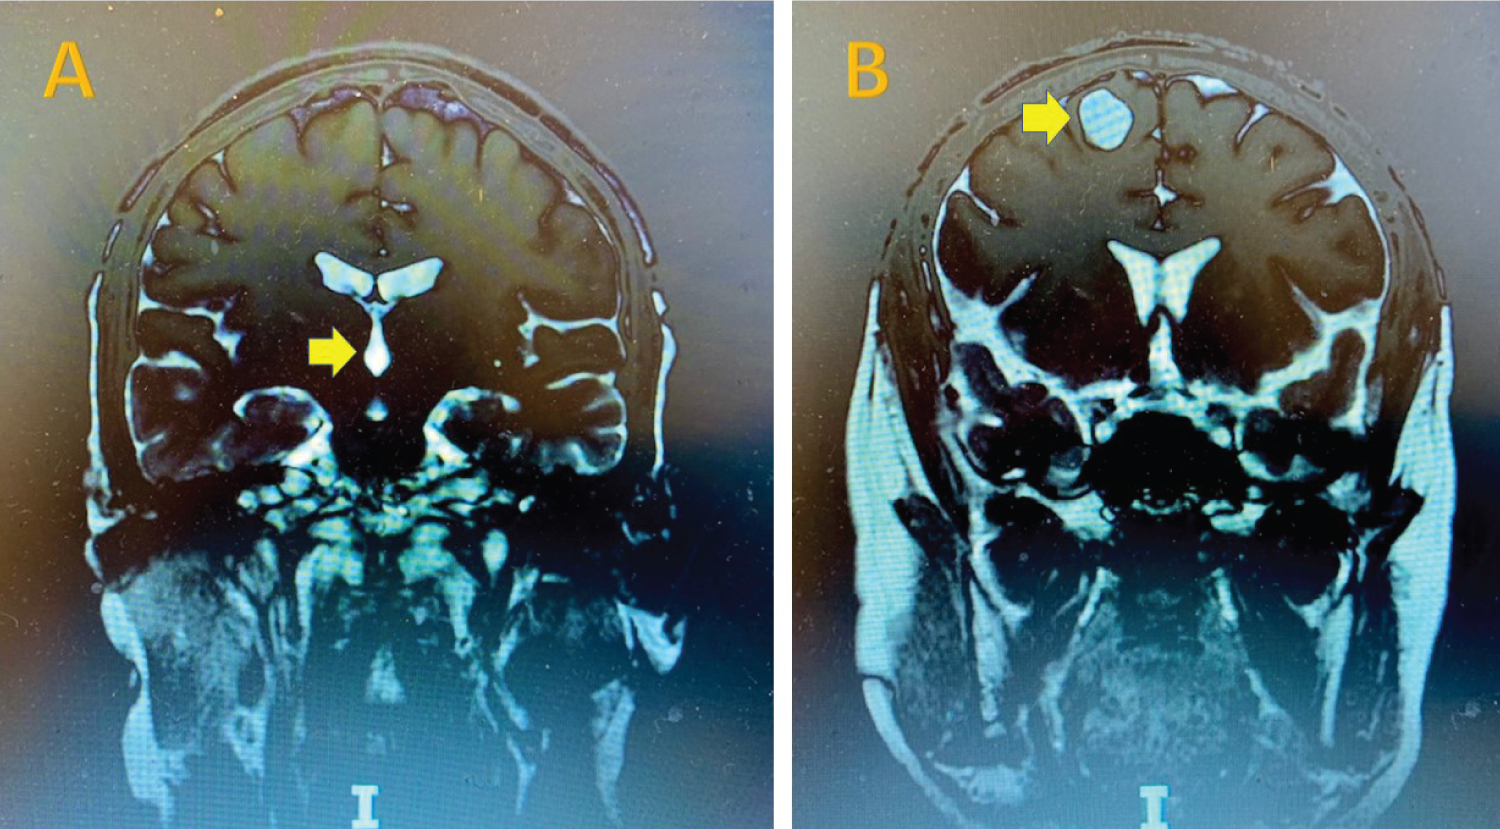

A thirty-year-old male patient from Honduras with a history of chronic HA was in his usual state of health until he experienced two generalized tonic-clonic seizures. He was treated with the anti-seizure medication levetiracetam and dexamethasone for epilepsy and presumed brain inflammation from NCC. He was subsequently referred to our hospital for further evaluation. The brain MRI revealed two major lesions: A viable parenchymal cyst lesion (14 × 17 × 20 mm) in the right frontal lobe with surrounding edema and an intraventricular cyst lesion within the fourth ventricle. There were also multiple calcified brain lesions in subarachnoid space (Figure 1). He was found to be positive for cysticercus antibodies but HIV, toxoplasma, strongyloides, histoplasma, cryptococcus and TB titers were all negative. His lab results, examination and imaging studies confirmed the patient's diagnosis of neurocysticercosis.

Figure 1: Cystic lesions on MRI. 4th ventricle and right frontal lobe scoleces in cysts with arrows.

Typically, NCC invasion of the subarachnoid space predominates, followed by the parenchymal, intraventricular and spinal forms. Ventricular system involvement of NCC usually causes ventricular dilatation and hydrocephalus that require surgical intervention. Studies have shown a strong association of seizure onset with the presence of active cysts/calcified lesions, especially multiple cysts with calcification in the frontal and temporal lobes. The recurrence rate of seizures with calcified lesions are much higher than that with lesion resolution [2,6,8,12]. Calcified NCC can cause brain inflammation from host immunologic response. Blood-brain barrier breakdown, cortical necrosis, space-occupying effect of NCC and reactive gliosis around calcified NCC can all lead to the chronic epileptogenic process [12,13]. The predictors of calcification usually include NCC lesion size > 10 mm, delayed treatment and inadequate dosage of medication [6]. Our patient reported long-term headaches since childhood and with recent onset of generalized grand-mal seizures. The MRI imaging was remarkable for one viable parenchymal cyst lesion (14 × 17 × 20 mm) in the right frontal lobe with surrounding edema, an intraventricular cyst lesion within the 4th ventricle, and multiple calcified brain lesions.